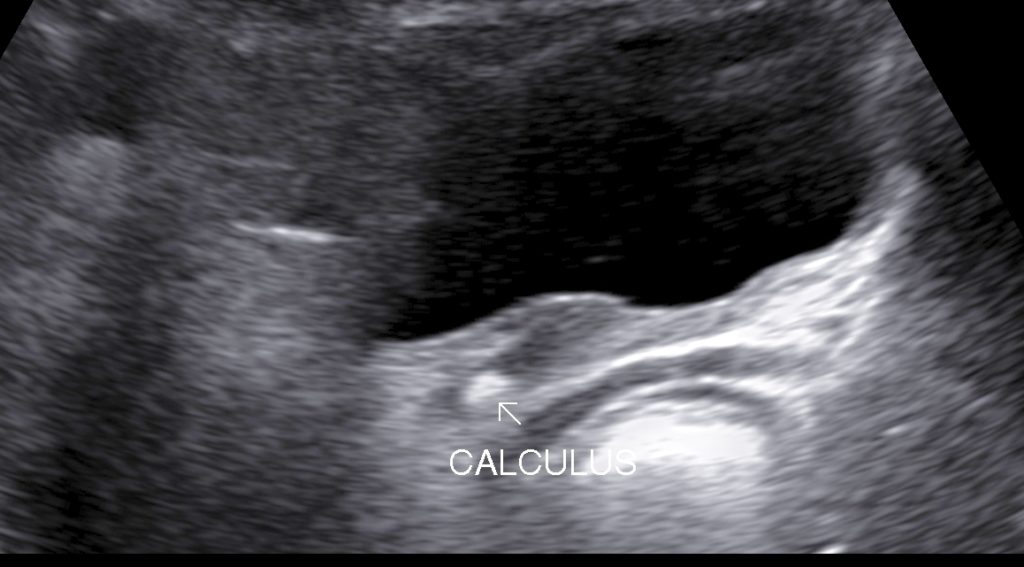

Upper ureteric & lower ureteric calculi can be visualized by sonography however middle ureteric calculus may not be visualized due to overlying gas shadows.

• Ureteric Calculi: